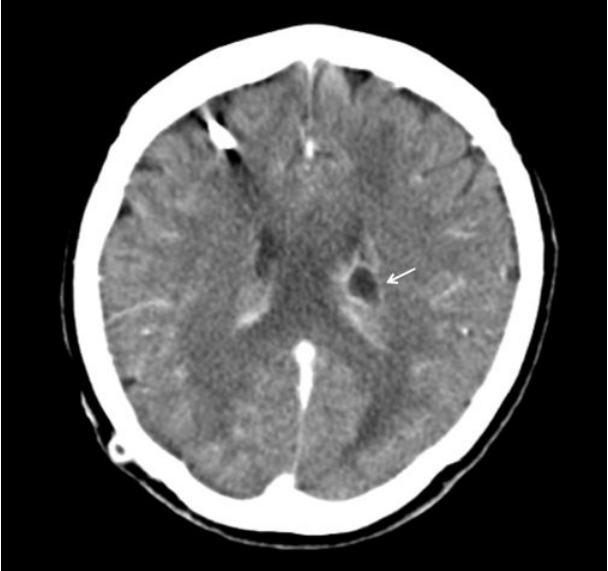

Figure 3.

Follow-up brain computed tomography showing that the abscess decreased in size (from 1.7 × 1.4 cm to 1.2 × 1.0 cm, arrow), and improvement of the periventricular edema.

74세 여자가 어지럼증으로 입원하였다. 뇌척수액의 결핵균 핵산증폭 검사에서 양성 소견을 보여 결핵성 수막염으로 진단되었으며 수두증을 동반하여 뇌실복강단락술을 시행하였다. 뇌척수액과 혈액에서 결핵균 외 다른 병원균은 검출되지 않았고, Cryptococcus 항원 검사와 India ink 염색은 음성이었다. 항결핵제 치료를 시작하였고 증세 호전을 보여서 퇴원하였다.뇌실복강단락술 시행 14주 후, 환자는 열감과 구토, 의식저하를 주소로 재입원하였다. 활력 징후는 혈압 120/80 mmHg, 심박수 76회/분, 호흡수 20회/분, 체온 37.7℃였고 의식은 기면 상태였다. 혈액 검사에서 백혈구 10,400/mm3 (중성구 56.1%), 혈색소 11.4 g/dL, 헤마토크리트 33.5%, 혈소판 441,000/mm3였고, 적혈구침강속도는 75 mm/h, 고감도 C-반응단백은 5.83 mg/dL였다. Human immunodeficiency virus 항체와 신속혈장리아긴 검사, Cryptococcus 항원 검사는 음성이었다. 뇌실복강단락을 통한 뇌척수액 검사에서 압력은 120 mmH2O, 백혈구 1.8/uL, 적혈구는 검출되지 않았으며 당 62 mg/dL (혈당 139 mg/dL), 단백질 40.1 mg/dL, 아데노신디아미네이스는 3.0 IU/L였다. 뇌 컴퓨터단층촬영에서 좌측 뇌실의 조영 증가와 주위조직의 부종, 좌측 뇌실내 도관 근위부에서 1.7 × 1.4 cm 크기의 변연부에 조영증강이 되는 낭성병변이 관찰되었다(Fig. 1). 뇌실복강 단락을 통한 복강내 감염의 진행을 확인하기 위하여 복부 조영증강 컴퓨터단층촬영을 시행하여 우하복부에 위치한 도관 말단 부위에서 4.7 × 2.8 cm 크기의 조영증강되는 벽을 지닌 낭종을 확인하였다(Fig. 2). 경험적으로 ceftriaxone 2 g/day와 혐기성균에 의한 혼합 감염의 가능성을 고려하여 metronidazole 1,500 mg/day를 정맥 투여하였고 입원 병일 3일째 뇌척수액 그람 염색에서 효모균이 관찰되어 fluconazole 200 mg/day를 추가로 투여하였다. 입원 병일 7일째 복부의 낭종에 대하여 진단적 복강경 검사를 시행하였다. 복강내 도관 말단은 4 cm 크기의 투명한 액체로 채워진 낭종 안쪽에 위치하고 있었으며 주변으로 유착이 관찰되었다. 낭종과 기존의 뇌실 복강단락을 제거 후 체외 내실 배액관으로 교체하였다. 뇌척수액과 혈액 배양 검사 결과에서 2회 연속으로 Cryptococcus neoformans가 동정되어 Cryptococcus에 의한 뇌막염으로 진단하였고 배양 검사와 핵산증폭 검사에서 결핵균은 동정되지 않아 amphotericin B 0.7 mg/kg/day를 정맥 투여하고 flucytosine 100 mg/kg/day를 경구 투여하였다. 입원 병일 12일째 복부 낭종 흡인액 배양 검사에서 Pseudomonas aeruginosa와 Klebsiella species가 동정되었고 뇌실내 도관 말단 배양 검사에서 Cryptococcus neoformans가 동정되었다. Pseudomonas에 대하여 ciprofloxacin 400 mg/day를 정맥 투여하였다. 입원 병일 19일째 시행한 뇌 컴퓨터단층촬영에서 뇌농양의 크기는 1.2 × 1.0 cm로 감소하였고 수두증은 호전 소견을 보였다(Fig. 3). 입원 병일 21일째부터는 열과 신경학적 증상이 호전되고 의식상태가 명료하여 amphotericin B와 flucytosine을 중단하고 fluconazole 200 mg/day로 교체하였다. 입원 병일 30일째 연속 3번의 뇌척수액 배양 검사에서 음성 소견을 보여서 체외 내실 배액관을 제거하고 새로운 뇌실 복강 단락 도관을 배치하였으며 경구 fluconazole 200 mg/day를 6개월 이상 투약 유지하기로 하고 퇴원하였다. 6개월간의 추적 관찰 기간 동안 환자는 특별한 증세나 재발의 소견 없이 지내는 중이다.